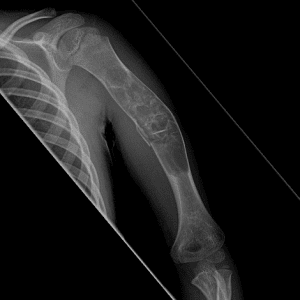

Pediatric Radiographs